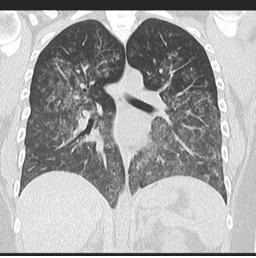

Difuzna alveolarna krvavitev zaradi vaskulitisa

Vir: radiopaedia.org